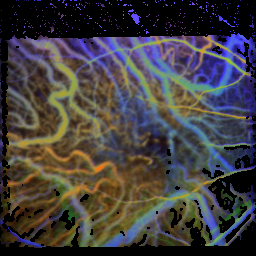

RGB images normalized to untreated patients with AMD

On this page, the colors in the images are normalized to the respective influx behaviour of untreated patients with AMD, so the colors visualize the influx relative to these patients (warm colors for rapid influx, cool colors for slower influx).

Patient with age-related macular degeneration, dry form

time of the maximum: 50.4 f ± 14.3%

visual acuity: 0.30